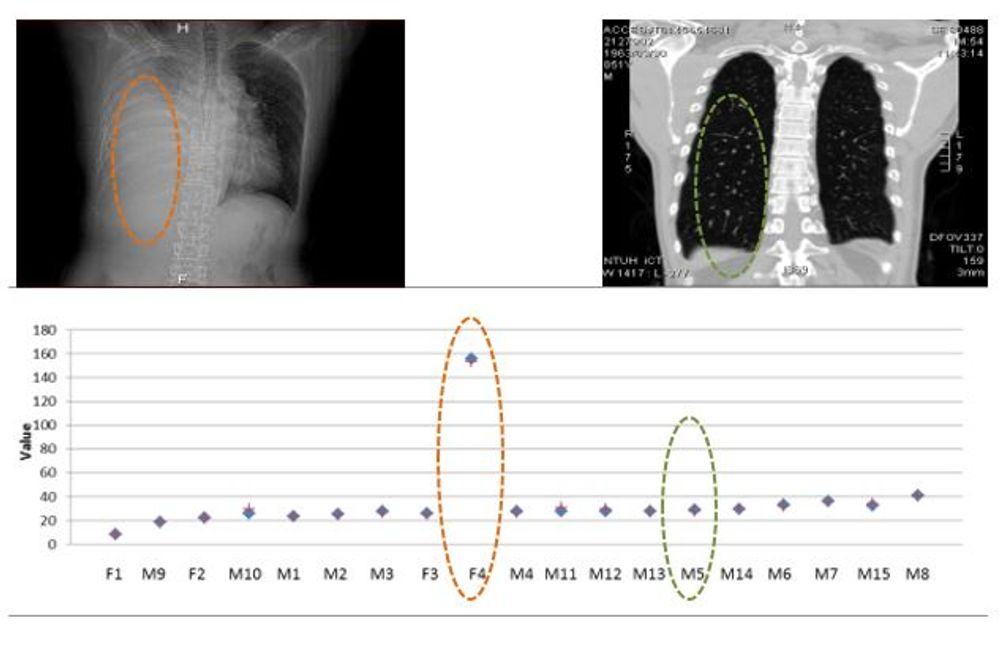

研究成果之醫療感測裝置,直接監測人體肋膜積水。

研究成果與X-ray比對。

【研發肋膜積水醫療感測器材Wearable pleural effusion sensing medical device】

一般肋膜積水的診斷方式為胸部X光檢查,胸腔超音波檢查以及胸部電腦斷層檢查(CT scan)。然而,大量照射X光對於身體抵抗力較差者可能具有危害健康的疑慮,且這些檢查儀器並非輕巧及隨處可用,因此我們過去數年間已完成開發輕巧不占空間之可攜式居家監測儀,以非侵入式之感測原理,量測身體內部組織成分的改變,判定積水程度以利進一步就醫或治療等措施。對於肺積水之病人,於疾病中晚期時由於行動較為不變,使用此攜性裝置可隨時監控其肋膜積水狀況,管理心臟衰竭患者身體之健康。此研究成果,已經技術移轉到鴻海永齡坤金公司,其集團正量產產品化中。